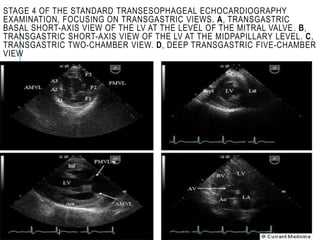

STAGE 4 OF THE STANDARD TRANSESOPHAGEAL ECHOCARDIOGRAPHY

EXAMINATION, FOCUSING ON TRANSGASTRIC VIEWS. A, TRANSGASTRIC

BASAL SHORT-AXIS VIEW OF THE LV AT THE LEVEL OF THE MITRAL VALVE. B,

TRANSGASTRIC SHORT-AXIS VIEW OF THE LV AT THE MIDPAPILLARY LEVEL. C,

TRANSGASTRIC TWO-CHAMBER VIEW. D, DEEP TRANSGASTRIC FIVE-CHAMBER

VIEW